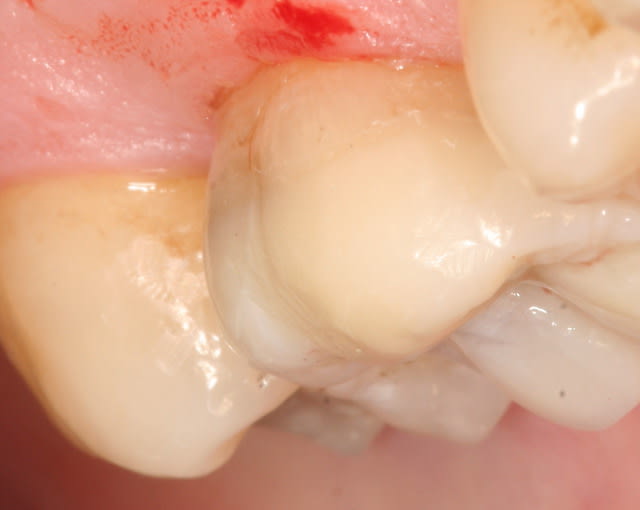

heu... tu confonds je pense avec la gingivectomie de la gencive linguale, afin de retrouver une limite compatible avec le collage

c'est soit pour remonter la marge et me simplifier l'empreinte (comme ça je peux faire ça comme un cochon) et le collage. Ou alors pour diminue l'épaisseur de ceramique en vue du collage que photo.

Ensuite ça créer ce que l'on appelle l'IDS (immediate dentin sealing) qui permet de protéger la dentine et la pulpe et soit disant améliore le collage.